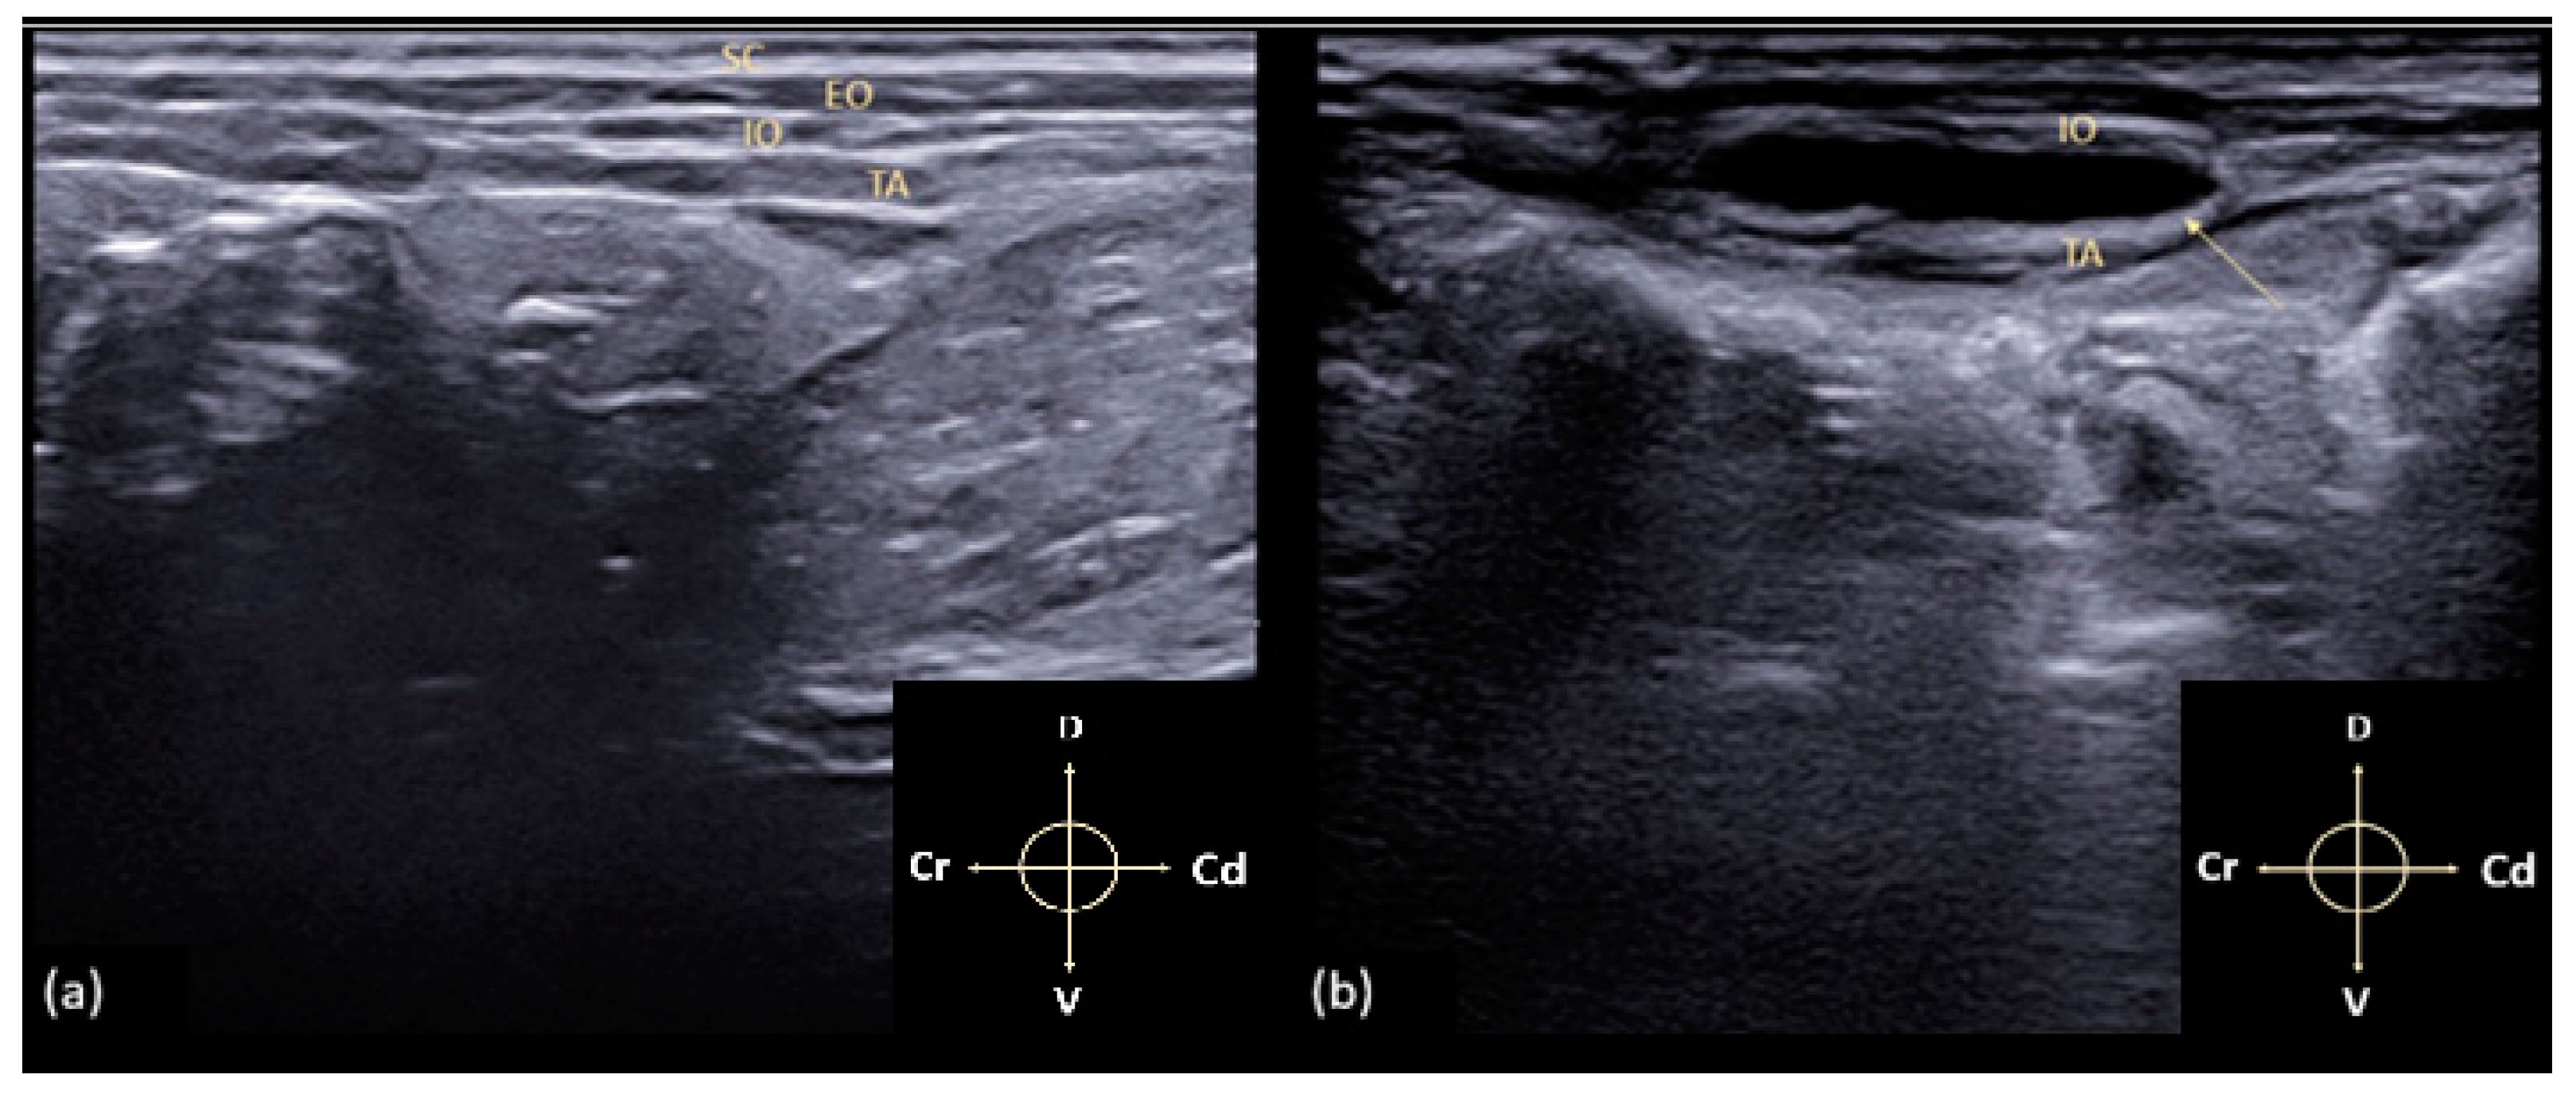

2.1. US-Guided TAP Block

3.1. US-Guided TAP Block